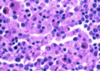

What is this slide stained with?

What stains:

- Purple

- Red/pink

- Pale blue

- Dark blue

Purple = chromatin/nuceli and netrophil granules

Red/pink = Erythrocytes/eosin granules

Pale blue = Lymphocyte/monocyte plasma

Dark blue/purple = Basophil granules